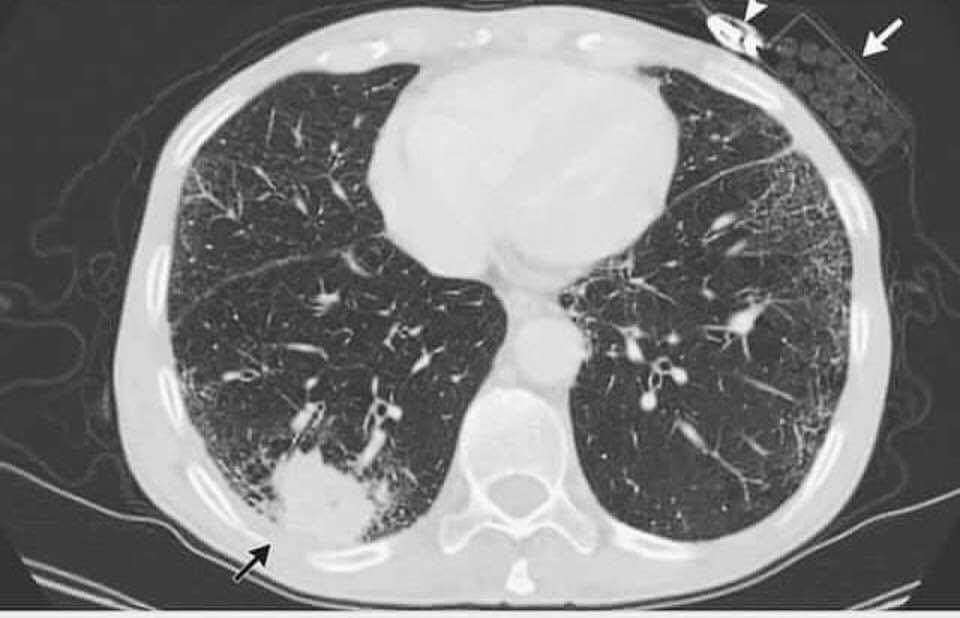

أكد الدكتور عاصم منصور مدير عام مركز الحسين للسرطان في قراءة تحليلية لصورة أشعة نادرة أنه لا توجد جريمة في علم الجنايات دون جثة وسلاح مشيرا إلى أن الصورة كشفت بوضوح عن ورم سرطاني في الرئة يمثل الضحية بينما ظهر سلاح الجريمة المتمثل بعبوة سجائر وولاعة تركها المريض في جيبه سهوا وأضاف منصور أن الخطوط البيضاء الدقيقة المتقاطعة في الرئتين تعكس آثارا زمنية طويلة للتدخين مما يثبت وجود علاقة جرمية قديمة بين الجاني والضحية واصفا الصورة بأنها أبلغ من ألف كلمة في التوعية من مخاطر التبغ وأضراره الفتاكة على الجسم البشري